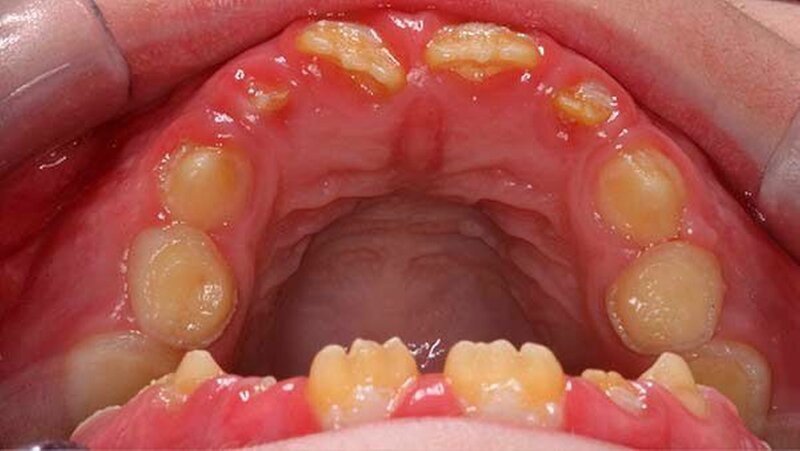

Der zehn Jahre alte Junge stellte sich an der Klinik wegen Schmerzen im ganzen Mund vor. Zusätzlich klagte der Patient über die eingeschränkte Möglichkeit Speisen ab zu beißen (Abbildung 1a und Abbildungen 3a und 3b). Die Familienanamnese ergab eine nahe verwandtschaftliche Verheiratung in der Familie. Das dentale Erscheinungsbild konnte von den Eltern des Patienten in der Verwandtschaft jedoch ausgeschlossen werden.

Der klinische Befund zeigte an beiden Dentitionen eine rauhe, zum Teil verminderte, bis fehlende Schmelzdicke und eine teilweise bräunliche Zahnverfärbung. Letztere wurden auch durch exogene Pigmenteinlagerung verursacht (Abbildung 1b und Abbildung 2).